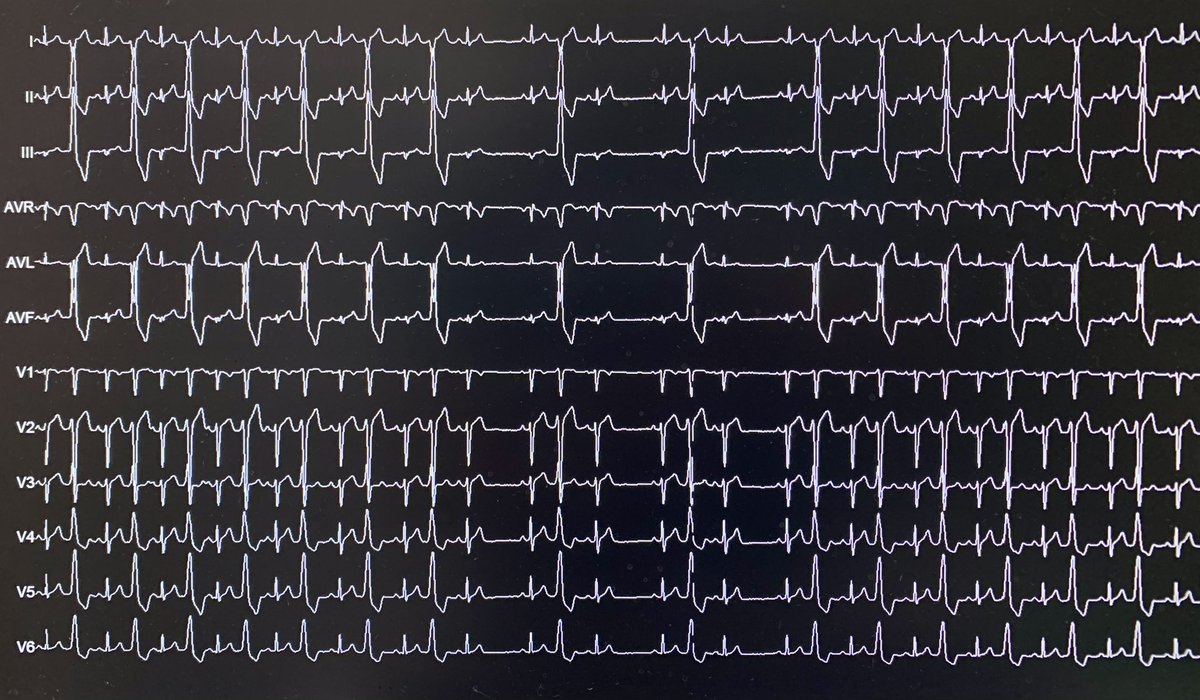

Pinwheel 🎡 flutter in the RSPV before starting PFA PVI. Patient presented in this rhythm and ECGs going way back show only this AFL, sometimes 2:1 and sometimes Wenckebach. Do you isolate the RSPV and call it good, isolate both RPVs, or perform the full PVI as planned? #EPeeps